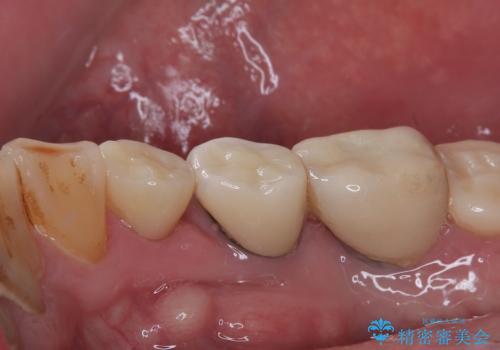

- 食事中に歯が欠けてしまったとのことで来院された患者様です。

以前詰めた材料が外れたか、歯が欠けたのかは分かりませんが、欠損している状態でした。

再度詰め物での処置を行うと引き続き欠けるリスクが高いため、高強度のフルジルコニアクラウンにて補綴治療を行うこととしました。

フルジルコニアクラウンは高強度であるため、クラウンの破損リスクは低減されましたが、失活歯(神経を取り除いた)では歯根破折リスクが高いとされており、抜歯の可能性が高まるため適用されません。